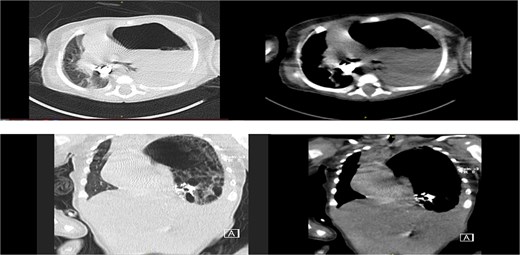

Chest radiograph showed an opaque left hemithorax with mediastinal shift to the right and a large air-fluid level, raising suspicion for diaphragmatic hernia with gastric herniation (Fig. 1a). Abdominal ultrasound revealed a cystic structure in the left thorax consistent with the stomach (Fig. 1b). Computed tomography confirmed a left posterolateral diaphragmatic defect with herniation of the stomach into the thorax, consistent with Bochdalek hernia and tension gastrothorax (Fig. 2).

(a) Opacified left hemithorax with shifting of the mediastinum to the right side due to possible left diaphragmatic hernia also there is right perihilar infiltrate. (b) US showed: Large cystic structure noted in the left side of chest likely stomach, diaphragmatic hernia cannot be ruled out.

Axial, coronal CT chest revealed: Left diaphragmatic hernia (Bochdalek hernia) stomach herniation to the left hemithorax with a shift in the mediastinum.